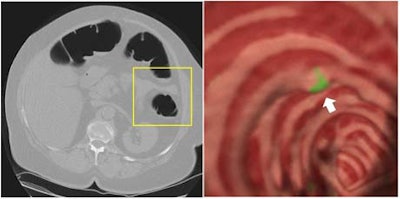

![]() |

"The GC feature is particularly effective in differentiation of polyps from stool, one of the leading causes of false positives," Yoshida wrote. "The soft-tissue density within a small polyp tends to increase from the colonic air toward the center of the polyp. Therefore, gradient vectors tend to converge at the center of the polyp, thus showing a high GC value."

The internal texture pattern of stool tends to be more inhomogenous than that of polyps. This inhomogeneity causes the directed gradient vectors to be directed randomly rather than toward any particular point. It is these differing GC values that enable false positives due to stool to be differentiated from true polyps, Yoshida wrote.